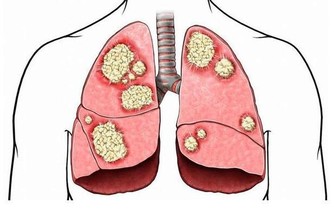

我國目前的癌症發生率,肝癌排第二,僅次於肺癌,而且大家可能都知道,肝癌的形成有三步:慢性肝炎→肝硬化→肝癌,因此,肝硬化作為肝癌來臨前的一道“重要防線”,一定要引起重視。